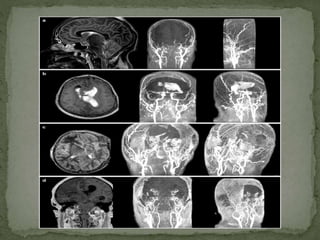

Trans temporal (a) and

trans orbital (b)

blood flow profiles

measured continuously